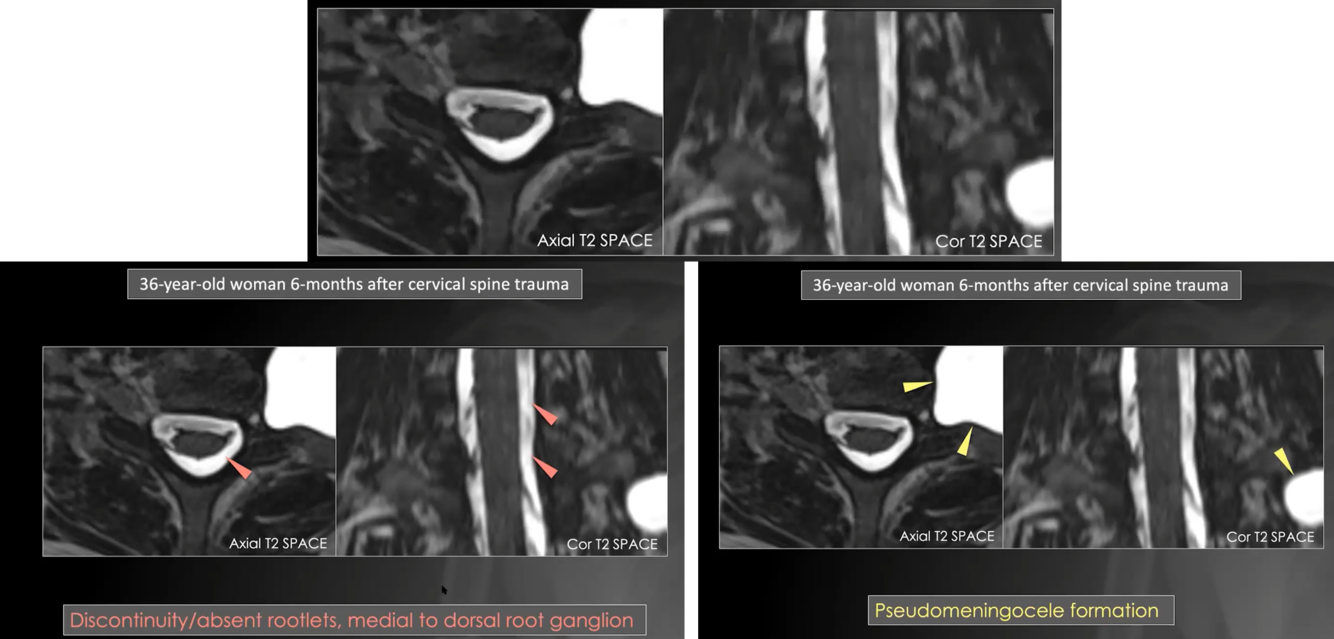

Preganglionic injury

preganglionic injury. discontinuity/absent rootlets, medial to dorsal root ganglion